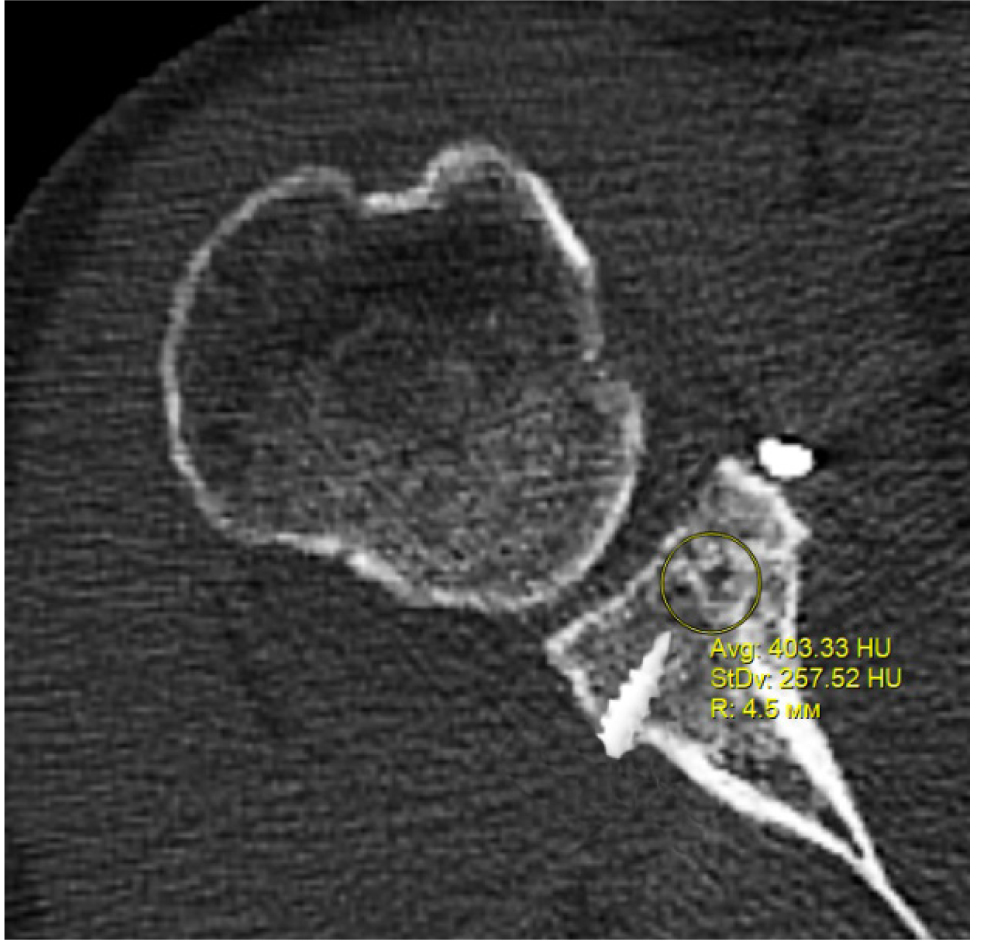

В программном обеспечении, на аксиальных КТ срезах оперированного плечевого сустава, выбирали инструмент «круг», который позволял посчитать среднюю плотность тканей внутри круга в единицах Хаунсфильда. Шкала единиц Хаунс-филда (HU) – шкалалинейного ослабления излучения по отношению к дистиллированной воде, рентгеновская плотность которой была принята за 0 HU (при стандартных давлении и температуре). Круг устанавливали таким образом, чтобы одна его половина была заполнена тканью гленоида, вторая половина тканью трансплантата (рис. 1–3). Оценивали плотность тканей над проксимальным винтом, между винтами, под дистальным винтом. Полученные данные анализировали с помощью пакета Microsoft Excel.

Рис. 1. Оценка плотности ткани под дистальным винтом

Рис. 2. Оценка плотности ткани между винтами

Рис. 3. Оценка плотности ткани над проксимальным винтом